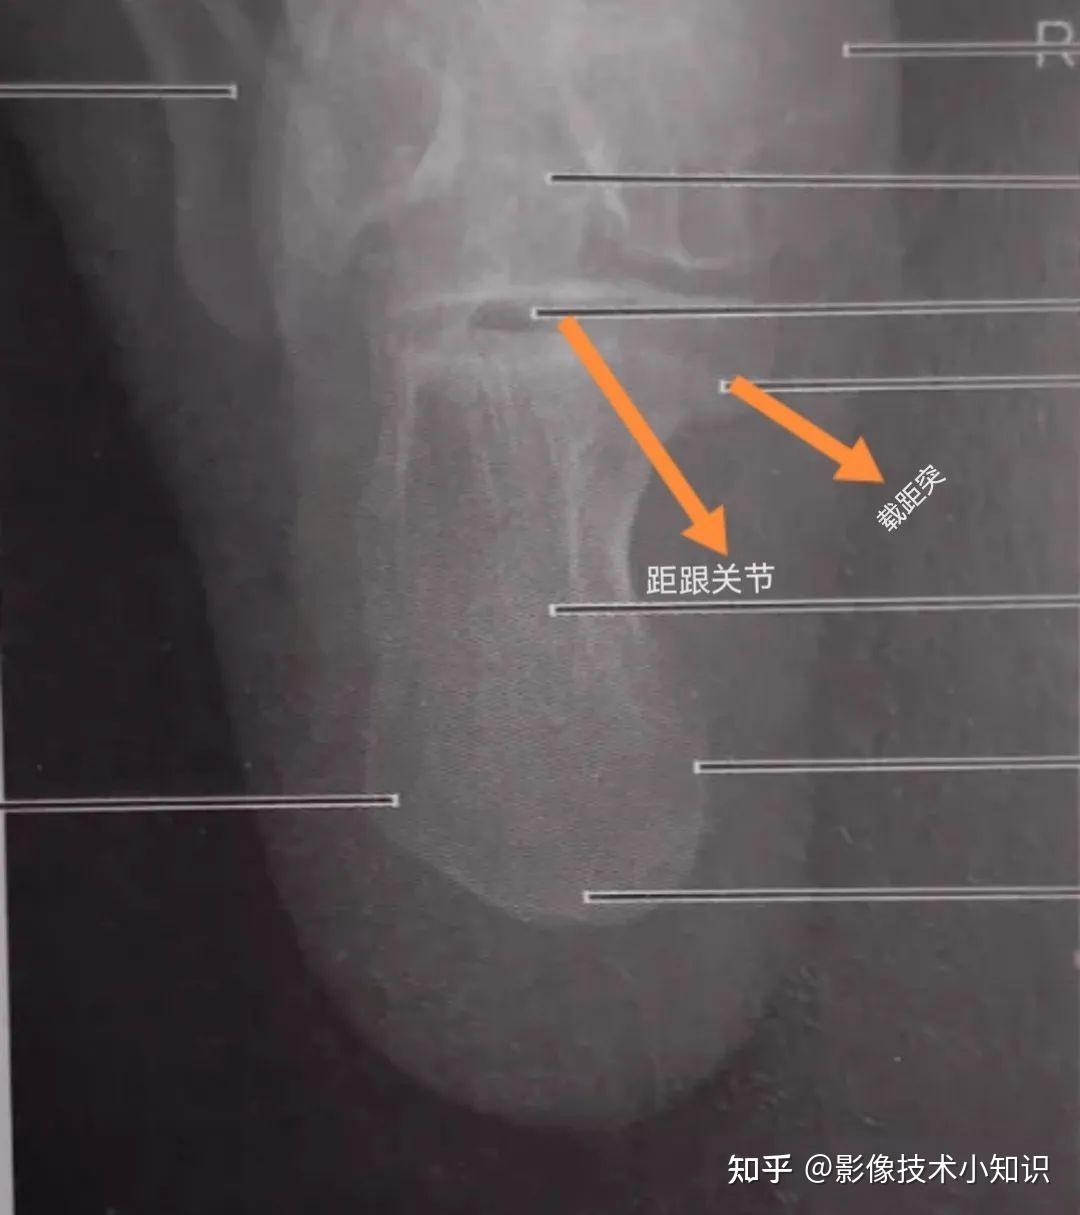

跟骨轴位解剖

跟骨解剖